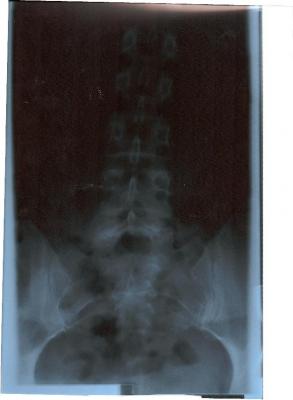

Ach so bevor ich vergesse: von meinem Rücken bestehen 4 Röbis, die den gesamten Rücken zeigen. Das Bild von der LWS ist eigenartig: erst unten gerade und dann geht sie schräg nach rechts hoch. Meine Orhopädin meint, die LWS sei kerzengerade, der FA aus Bochum meint, da hätte ich beim der Aufnahme einen Druck von links bekommen (ich stand aber allein und - für mich - gerade vor dem Gerät. Mich hat nichts und niemand gedrückt - interessiert die Ärzte aber nicht). Leider konnte ich dem Menschen in Bochum auch nur die zeigen, da die CD`s noch im Krankenhaus unterwegs sind.

Ich kann auch das Röntgenbild, wo die WS so schräg ist, einstellen. Du klingst nach viel Erfahrung und kannst sicherlich besser beurteilen als ich!

Hier ist das Röbi wo die Ärzte meinen, die LWS sei kerzengerade:

Die Röntgenbilder habe ich nochmal reingestellt. Sorry, das mit dem Bild verkleinern wusste ich nicht. Ich hab die Bilder zwar in der falschen Reihenfolge eingestellt, aber ich hoffe, dass das nicht tragisch ist: zuerst also das untere Bild (mit Becken), dann das obere für den weiteren Verlauf. Alles wieder im Testforum!

Zum zum Röbi an sich: Es ist wirklich komisch, wie schief das nach oben geht. Ich vermute daher, dass deine eigentliche Krümmung darüber, also in der BWS sitzt oder du eine langgezogene Krümmung hast, die in der BWS weitergeht und dann wieder zur Mitte geht. Aber genau deshalb braucht man eine Ganzwirbelsäulen-Aufnahme!!

ich wollte erst schauen, ob das mit den Bildern funktionert - daher Testforum. Der erste Versuch ist ja auch schief gegangen, doch im Testforum problemlos löschbar. Jetzt hat es geklappt, daher habe ich sie jetzt auch hier. So können sich auch andere dazu äußern (obwohl Deine Meinung schon sehr fachfraulich klingt und ich fast glaube, dass mein Schicksal besiegelt ist!!!). Jedenfalls tut es mir gut, dass jemand anderes auch meint, dass meine WS eben doch nicht kerzengerade aussieht - ich freue mich (dachte nämlich schon, ich wäre bekloppt).

- Dateianhänge

- Bild 1 LWS.JPG (11.53 KiB) 13654 mal betrachtet

- Bild 2 LWS.JPG (9.9 KiB) 13654 mal betrachtet

es wäre wirklich interessant, wie deine Wirbelsäule im Ganzen aussieht. In der LWS hast du zumindest schonmal keine Rotation, was positiv ist. Evtl. ist es ja nur eine Fehlhaltung oder eben eine typische Begleit-Skoliose bei Rundrücken. Deshalb ist auch ein seitliches Röntgenbild zur Diagnostik notwendig.Jedenfalls tut es mir gut, dass jemand anderes auch meint, dass meine WS eben doch nicht kerzengerade aussieht - ich freue mich (dachte nämlich schon, ich wäre bekloppt).

Ansonsten sieht meine Mutter dem Termin sehr ruhig entgegen während ich schon jetzt eine leichte Nervosität fühle. Wir haben von uns beiden Röbis der LWS (auf CD, leider komme ich mit dem Runterladen nicht klar und kann sie nur einsehen aber nicht abspeichern). Meine Mutter hat den gleichen "Bogen" wie ich - nur dass bei ihr die Wirbel sich drehen. Außerdem sieht man bei meinr HWS einen deutlichen Bogen nach links (die LWS geht ja nach rechts bei uns beiden). Ich glaube, so langsam muss ich mich mit Tatsachen anfreunden